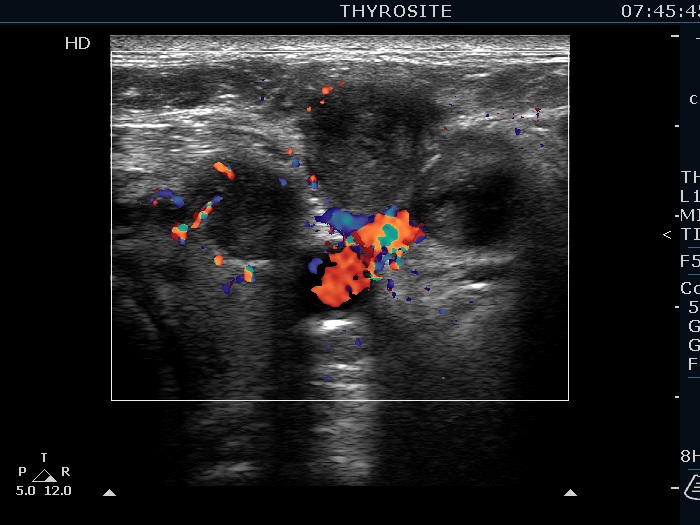

Thyroid cancers - case 1066 (ultrasonographic picture 13)

Lateral to the left lobe, transverse scan, color Doppler mode. The vascularity is not specific.